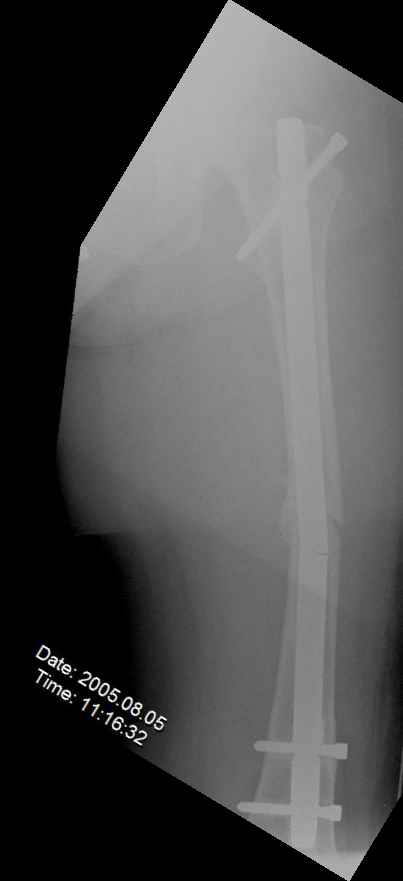

May I have some advice on the following case? Middle aged woman, No chronic medical problems, +tobacco use - but she promises she's going to quit! Original MVC in late 1990's, initial rod failed, and 2 subsequent exchanges failed (most recently shown in attached jpgs.)

Most recent one (6/2002) was apparently an open nailing to remove last broken nail, but no grafting was performed in conjunction. Now sent to me with broken 14mm R/T nail in place.WBC, Hgb, Chemistries normal.ESR 34CRP 4.2No other apparent locus of infection.I was considering a staged approach - removing nail and screws and obtaining cultures.If negative, proceed with exchange nailing with open grafting +/- BMP, But how best to deal with that pedestal distally and avoid anterior breech near patella? If positive cultures, what would be best option?Thanks. Tom Schaller Kalamazoo, MI.

In my opinion, there is no nail strong enough to tolerate a varus deformity of femur after nailing. The AP view of the distal femur shows that the femur has been repeatedly nailed in varus. The tip of the nail is short and lateral in distal lateral metaphysis. It should be central over the intercondylar notch and buried in the distal epiphyseal scar. This has resulted in constant bending forces on the nail (see the "windshield wiper" sign) and its eventual fatigue failure.

I would first determine the degree of varus deformity with a long standing AP x-ray. After nail removal, irrigation, debridement and reaming of the nonunion, specimens would be sent for pathology and culture. If there was any sign of infection, placement of custom made antibiotic nail e.g.

for two or three weeks would be performed before an ORIF plate fixation with Judet decortications and bone graft.

My first definitive treatment choice would be a long lateral tension band plate with insertion of proximal screws directed proximally at an angle of about 25-30 degrees. Correction of the varus would be accomplished by using a tensioning device distally or compressing with two eccentrically placed distal screws simultaneously as shown in Lawrence Webb's OTA BFC lecture

or two distal screws directed distally. Fixation would be completed by a pair of locking screws each side of the nonunion..

My second choice would be an Ilizarov compression over nail if there is familiarity with both nailing and Ilizarov technique.